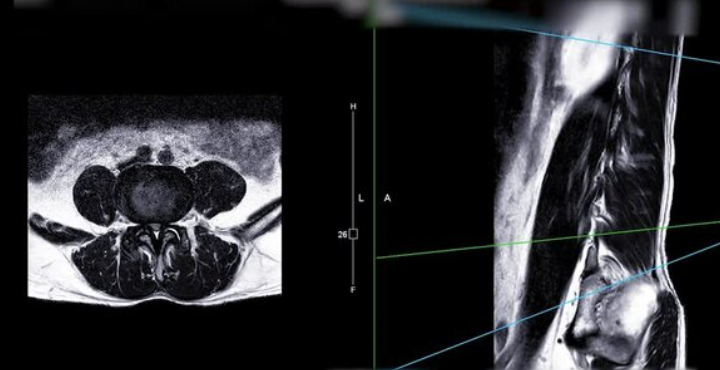

중요한 것은 적절한 진단을 받는 것입니다. 의사는 환자의 증상을 평가하고 MRI나 CT 스캔과 같은 영상 진단을 통해 허리디스크의 정도를 확인할 수 있습니다. 이를 통해 가장 적합한 치료 방법을 결정할 수 있습니다.